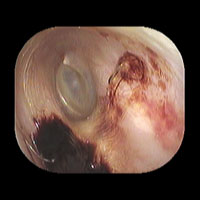

左真珠腫性中耳炎

左耳に白い真珠腫がみられます。外耳道から真珠腫をできる限り摘出しました。CTを撮影し、根治的な手術が必要でしたので、総合病院耳鼻咽喉科にご紹介し全身麻酔下に手術を行いました。

外耳道から清掃した後